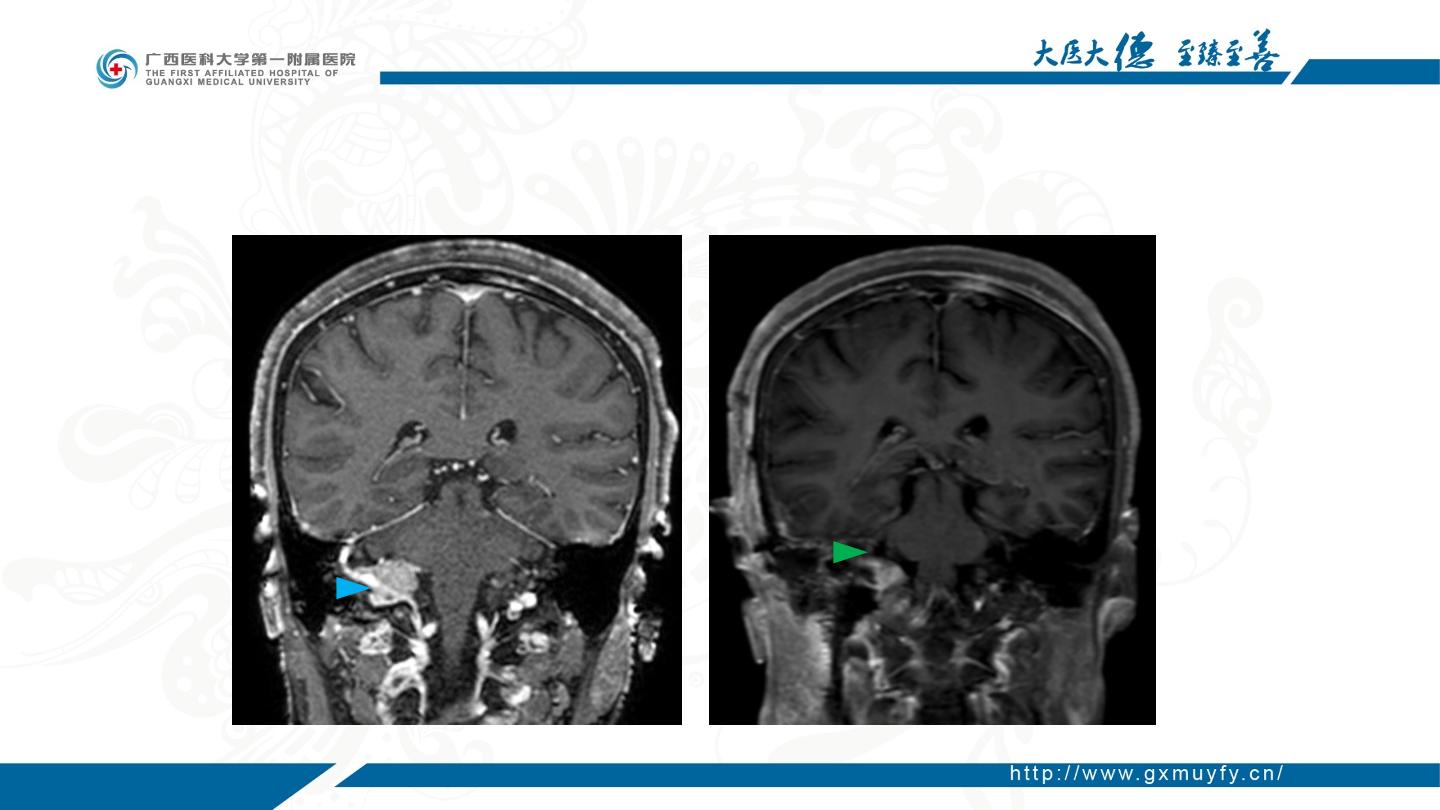

耳后经颞入路切除颈静脉孔区脑膜瘤